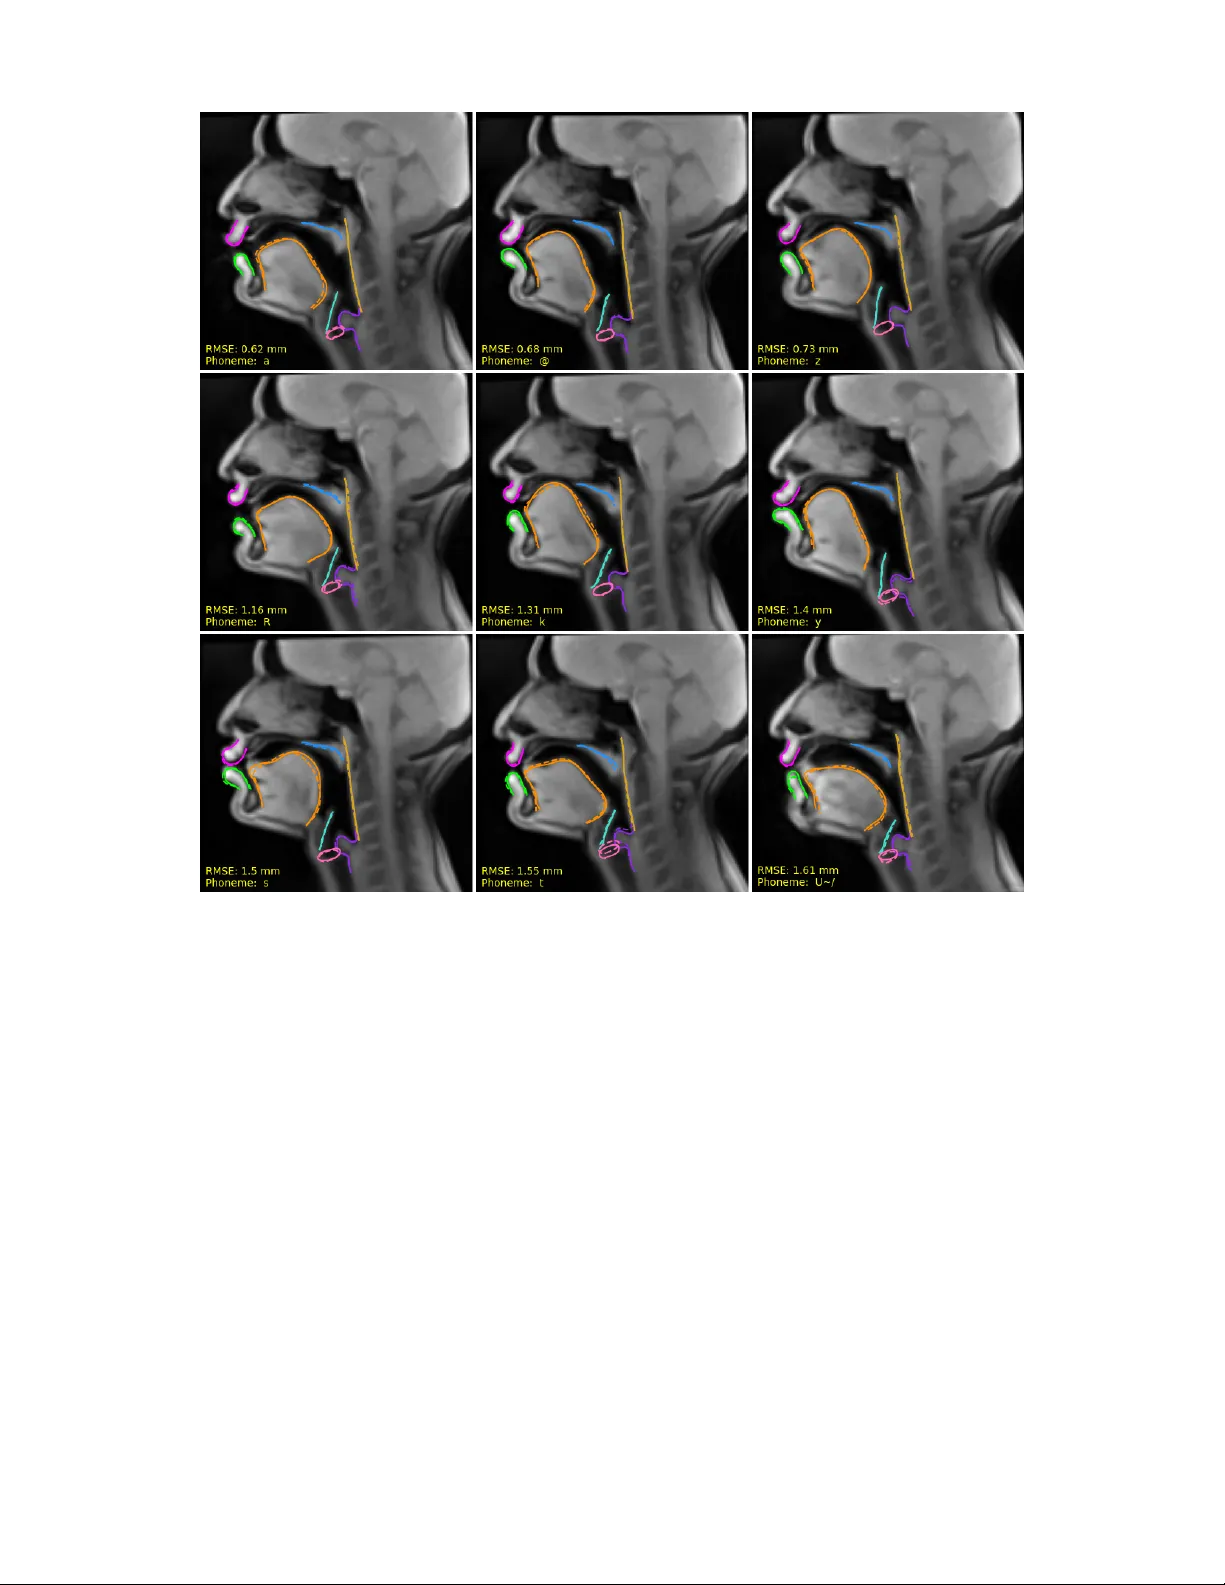

본 연구는 실시간 MRI(RT‑MRI) 영상에서 자동 추출한 조음기 윤곽선을 이용해 음성 신호를 조음 움직임으로 역변환하는 방법을 제안한다. Bi‑LSTM 모델에 MFCC, LCC, HuBERT 임베딩을 입력으로 사용하고, 데이터 양을 10분부터 3.5시간까지 변화시켜 성능을 평가하였다. 평균 RMSE는 1.48 mm(픽셀 크기 1.62 mm)로, 전체 성대‑입술 구간을 포함한 완전한 조음역변환이 가능함을 보여준다.

본 논문은 음성 신호를 이용해 전체 성도(성대부터 입술까지)의 조음 형태를 복원하는 ‘음성‑조음 역변환’ 문제에 접근한다. 기존 연구는 주로 전자기식 조음계(EMA)를 사용했으며, 이는 센서 수가 제한되고 전방 조음만을 측정한다는 근본적인 한계가 있다. 이러한 제약을 극복하고자 저자들은 실시간 MRI(RT‑MRI) 데이터를 활용한다. RT‑MRI는 전신 조음 정보를 제공하지만, 이미지 자체를 직접 학습에 사용하면 픽셀 수준의 잡음과 고해상도 요구 등 여러 문제점이 있다. 따라서 저자들은 자동 윤곽선 추적(RCNN 기반)으로 8개의 주요 조음기와 2개의 기준 랜드마크를 50점씩 2차원 좌표로 변환하고, 이를 정규화하여 모델 입력으로 사용한다. 이 과정에서 추적 오차는 평균 1 mm 수준으로, 실제 조음 움직임을 높은 정확도로 포착한다.